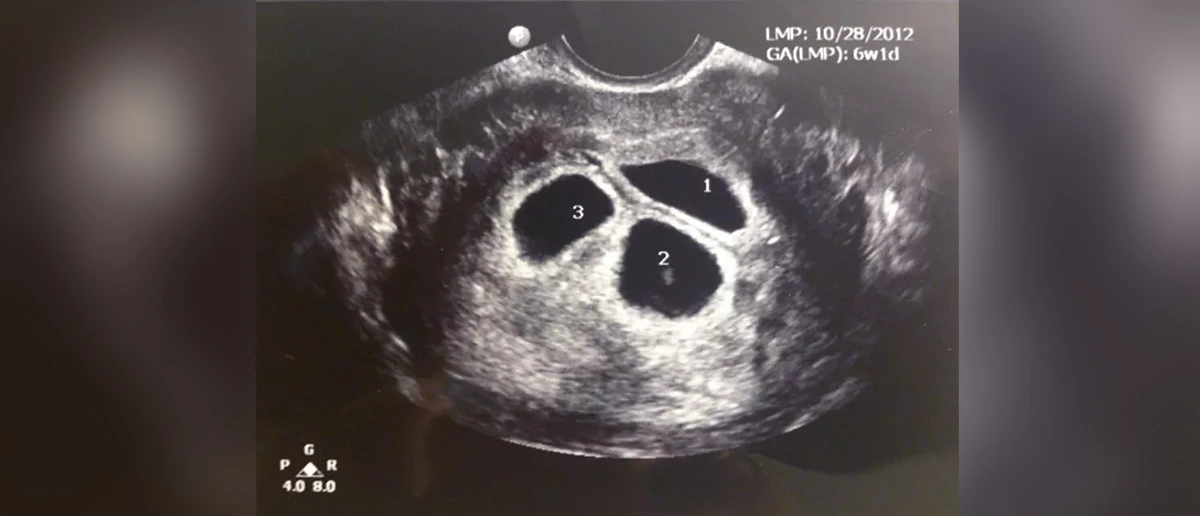

Tüp Bebek tedavilerinde çoğul embriyo transferi sonucu oluşan üçüz veya dördüz gebeliklerde anne ve bebeklerin sağlıklı geleceği açısından fetal redüksiyon tekniği uygulanarak gebelik sayısı indirgenebilmektedir. İkiz gebelik üstünde gebelik taşıyan birçok hasta kolay ve sağlıklı bir gebelik geçirebilmek ve aynı zamanda erken doğum riskini azaltmak için bu metoda başvurmaktadır.

Fetal redüksiyon gebeliğin 11.inci ile 12. haftasında uygulanır. İşlem karından veya vajinadan ultrason yardımıyla, izlenerek anestezi altında uygulanır. Gebelik keseleri incelenerek sonlandırılmasına karar verilen kese ince bir iğne yardımıyla aspire edilerek veya potasyum içeren bir ilaç ile bebeğin kalp boşluğuna iğne yardımıyla enjekte edilerek sonlandırılır. İşlem sonrasında bebeğin kürtajla alması gerekli değildir. Bebek vücut içeresinde zamanla küçülür ve genellikle kaybolur. Fetal redüksiyon sonrasında diğer bebekleri kaybetme riski % 1-5 oranındadır.